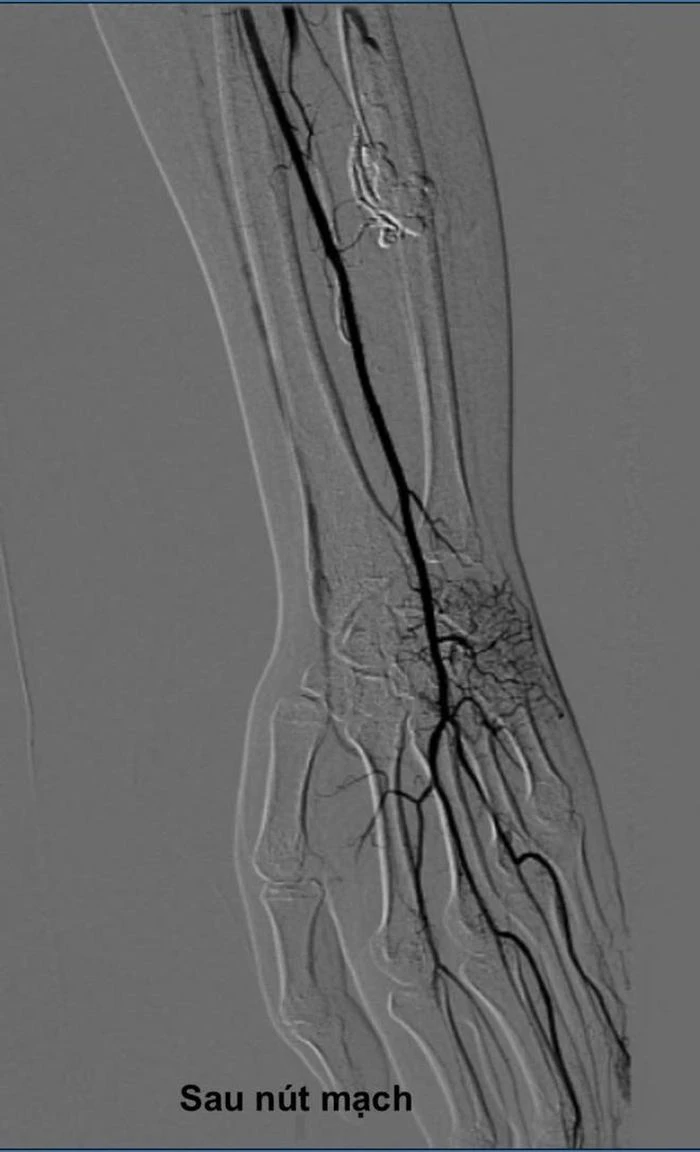

Dưới sự hướng dẫn của máy chụp mạch kỹ thuật số (DSA), bác sĩ sử dụng một cây kim rất nhỏ chọc trực tiếp qua da, đi chính xác vào ổ dị dạng nằm sâu trong cơ cẳng tay. Sau đó, cồn tuyệt đối (absolute ethanol) được bơm vào qua kim để làm xơ hóa và bịt kín hoàn toàn các mạch máu bất thường.

Ngay sau can thiệp, ổ dị dạng đã được bịt kín, dòng máu được tái lập bình thường. Chỉ sau vài ngày, các triệu chứng đau tê ngón tay của bệnh nhân Q. đã giảm rõ rệt.